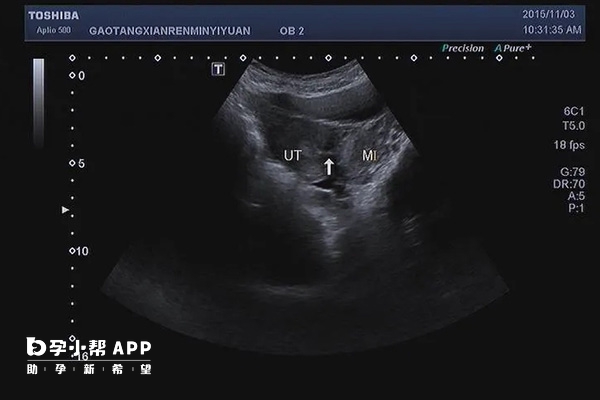

在临床上,单角子宫属于子宫畸形的一种,通过B超检查可以进行明确诊断,单角子宫超声诊断标准为,超声图像显示,仅一侧附中肾管发育,且多偏向该侧而成为单角子宫,另一侧附中肾管未发育。该侧的卵巢、输卵管、肾亦往往同时缺如。单角子宫有时候可能伴随有残角子宫情况。

如果女性患者,超声诊断为单角子宫伴随残角的话,除了以上超声表现外,还存在一侧腹中肾管发育正常,另一侧发育不完全而成残角子宫,可伴该侧泌尿道发育畸形。多数残角子宫与正常宫腔不相通,偶有两者间有狭窄管道相通。残角子宫内可有内膜,也可无内膜。内膜可有功能,也可无功能。

单角子宫在超声中可见子宫仅有一个宫颈与阴道相通,伴或不伴有残角子宫。子宫的左右角有一侧缺如。单角子宫还可以分为有无残角,残角子宫里又分为是否有宫腔、宫腔闭塞等。单角子宫畸形在一定情况下还能造成痛经、怀孕困难等。

其实单角子宫是女性子宫发育异常的一种类型,在超声检查中会表现为子宫仅有一个宫颈与阴道相交通,伴或不伴有残角子宫,发病原因主要是由于在胚胎时期,胎儿的生殖器官在发育过程中出现异常所致。单角子宫早期可无明显症状,女性在初次月经来潮后,可能会出现痛经,部分患者可能会有盆腔处疼痛、婚后不孕等表现。